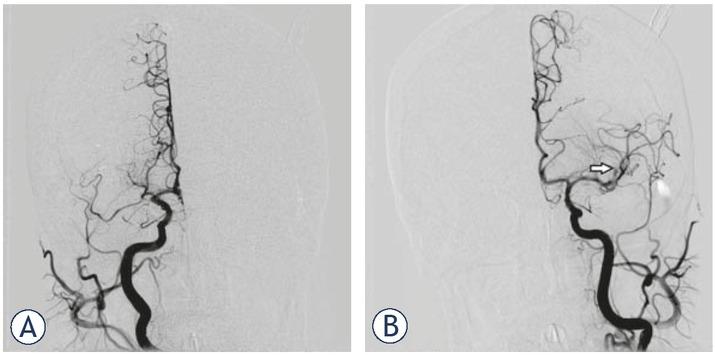

Conventional (digital subtraction) angiography confirmed right MCA occlusion with good collateral flow provided by the right anterior cerebral artery (ACA). However, the situation on the left side had changed. Namely, a complete recanalization of the carotid “T” occlusion was seen angiographically as a consequence of thrombolysis and distal migration of the thrombembolus (now presenting with proximal M2 segment occlusion of the major MCA branch). However, no collateral flow was observed despite complete left ACA patency (Figure 3). Endovascular mechanical recanalization with aspiration was successfully performed on the right side (Figure 4A). The same procedure was not performed on the left side because there was irreversible brain damage in the whole occluded arterial territory and a high risk of haemorrhagic complications. The postprocedural thrombolysis in cerebral infarction (TICI) scores were 3 (right MCA) and 2b (left MCA).

(A) Digital subtraction angiography (DSA) at the beginning of mechanical recanalization. Right internal carotid contrast injection confirming right M1 occlusion. (B) DSA at the beginning of mechanical recanalization. Left side contrast injection showing complete spontaneous recanalization of the carotid “T” occlusion with thrombembolar distal migration (occlusion of the proximal M2 segment of the major MCA branch) (arrow).